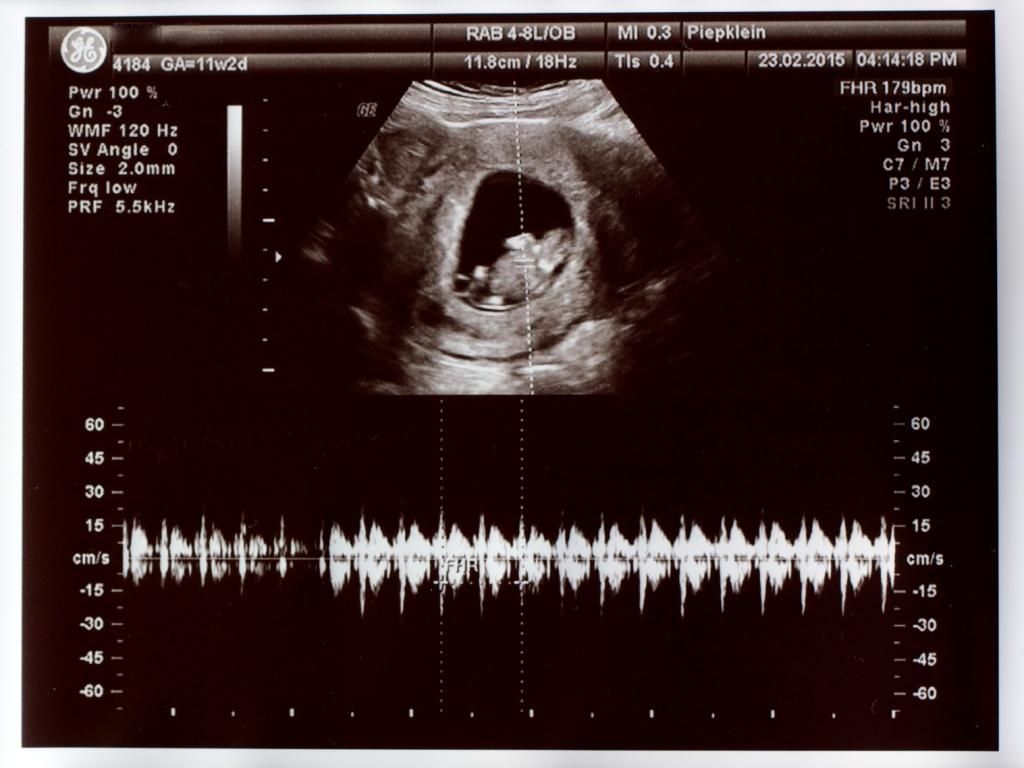

Wizzymaandag 23 februari 2015 @ 21:33

Vandaag voor de 2x een termijnecho gehad. De echoscopist was niet zeker van zijn zaak. Mijn baarmoeder is naar achteren gekanteld. Maar alle echo's lieten dezelfde termijn zien. Mijn uitgerekende datum mag naar 12-09-2015.

Nog gevraagd naar de nub-theorie maar dat vond hij maar een bakerpraatje -O- . Misschien kunnen jullie er wat uithalen. Al ligt hij/zij er niet goed voor.

Bij 9 weken

SPOILER

IMG_1172_zpsubeajnp8.jpg

IMG_1171_zpsqdkfjrn1.jpg

Bij 11 weken

IMG_1168_zps3f8bmibm.jpg

IMG_1166_zpsikkamaet.jpg

Tussendoor nog te horen gekregen dat de nekplooi niet verdikt is ^O^

Is nog iets te vroeg om de NUB vast te stellen, dat is tussen 12 en 14 weken. De NUB kan nog iets veranderen namelijk. Maar voor nu neig ik naar een jongen.

op beide foto's is geen nub te zien :) maar zoals eerder gezegd is het ook nog te vroeg voor nub. Overigens is nub gewoon wetenschappelijk bewezen, en zeker geen bakerpraatje. Alleen het is geen theorie die 100% zekerheid geeft over het geslacht.